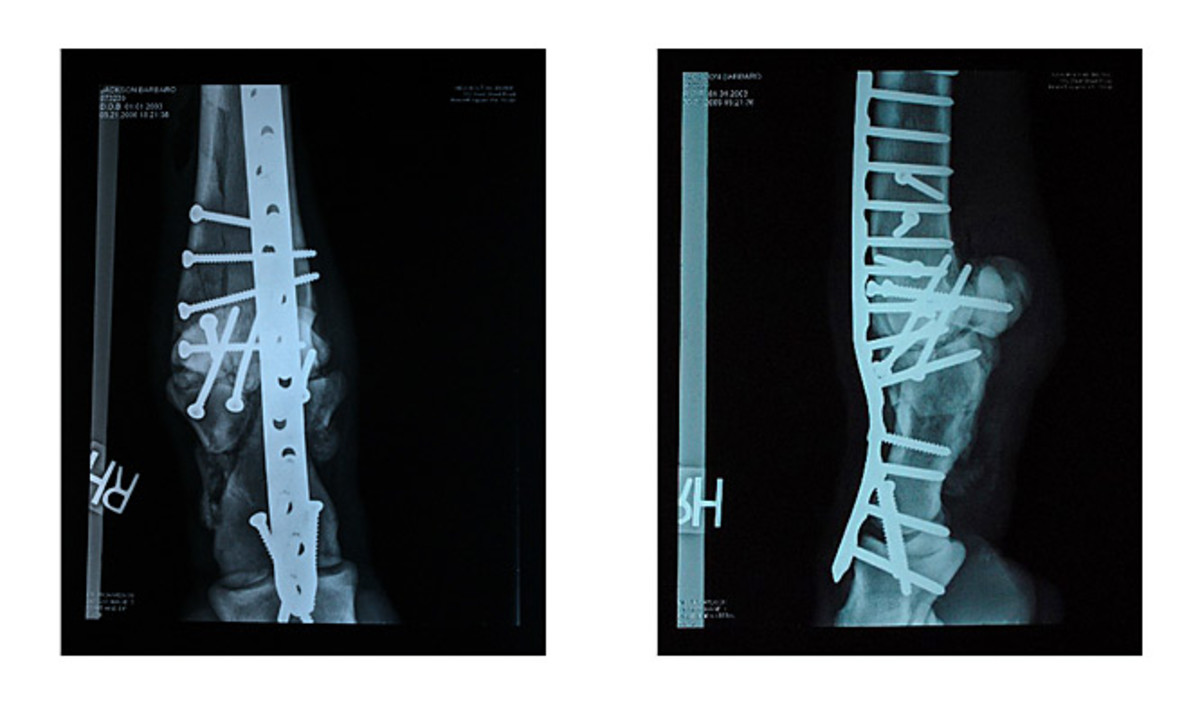

These X-rays, released by the University of Pennsylvania, show how Barbaro's right hind leg bone was held together using screws and plates.